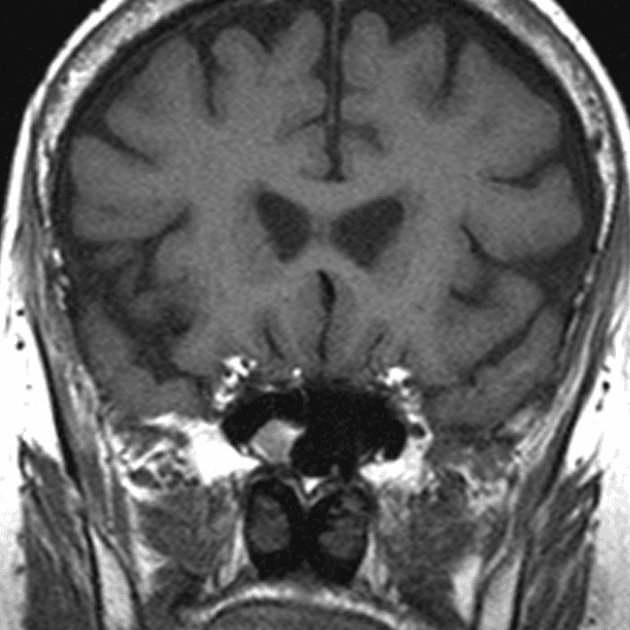

- Khối liên tục với cuống yên, làm giãn cuống này cả phía trên và phía dưới.

- Phù hợp với kiểu tăng quang đặc trưng và nằm trong cuống yên (infundibulum).

- Khối phù hợp với kiểu tăng quang đặc trưng và nằm trong cuống yên (infundibulum).

- Khối liên tục với cuống yên, làm giãn cuống cả phía trên và phía dưới.

- "Đặc điểm hình ảnh gồm khối u ranh giới rõ, tăng quang mạnh, liên tục với và làm giãn cuống yên."

U Pituicytoma là một loại khối u thần kinh đệm lành tính, phát triển chậm và hiếm gặp, xuất phát từ các tế bào pituicyte ở thùy sau tuyến yên hoặc cuống yên. Khối u thường biểu hiện như một tổn thương ranh giới rõ, tăng quang mạnh và liên tục với, đồng thời làm giãn cuống yên. Trên cộng hưởng từ (MRI), khối u thường có tín hiệu đẳng trên hình ảnh T1 và tăng quang đồng nhất sau khi tiêm thuốc cản quang. Việc không có dấu hiệu ác tính, không bệnh toàn thân và tổn thương ổn định dài hạn trên hình ảnh học làm tăng khả năng chẩn đoán u Pituicytoma, ngay cả khi chưa xác định bằng mô bệnh học. Các chẩn đoán phân biệt bao gồm u tuyến yên có liên quan đến cuống yên, u màng não và bệnh tổ chức bào Langerhans, những bệnh này có thể có hình ảnh tương tự. Tuy nhiên, vị trí đặc hiệu trong cuống yên và sự liên tục với cuống làm nghiêng về chẩn đoán u Pituicytoma. Điều trị thường mang tính theo dõi bảo tồn, đặc biệt ở bệnh nhân không có triệu chứng.